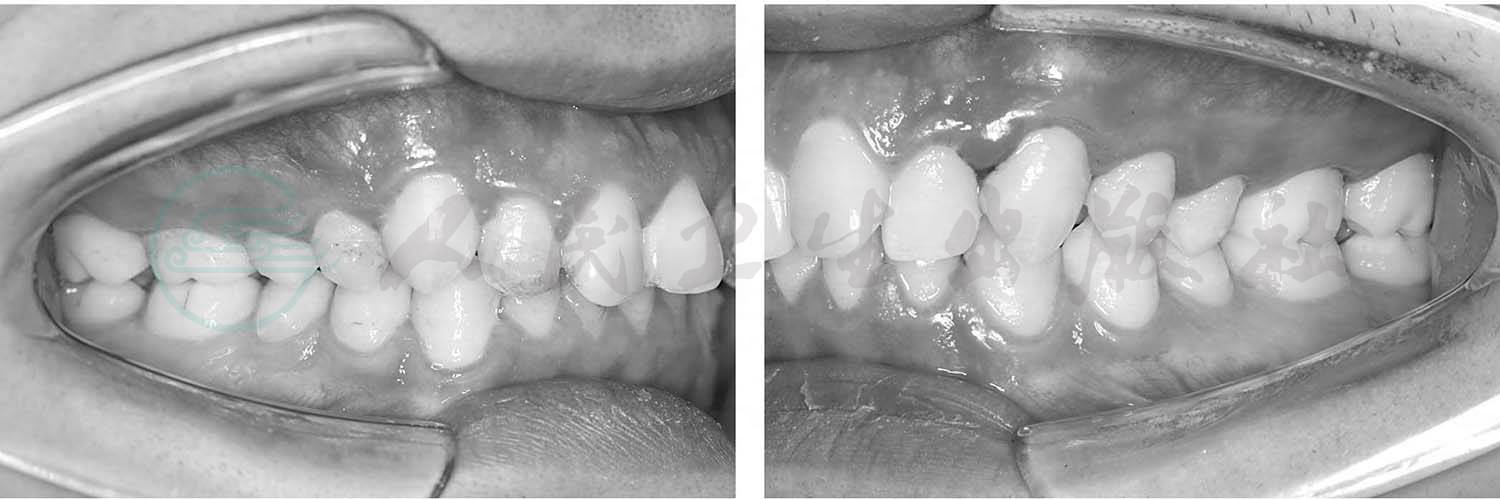

下牙弓及下颌处于近中位置。若下颌前移1/4磨牙或半个前磨牙的距离,即上第一恒磨牙的近中颊尖与下第一恒磨牙远中颊尖相对,称为轻度的近中错𬌗关系。若下颌向近中移位1/2个磨牙或1个前磨牙的距离,以至于上颌第一恒磨牙的近中颊尖咬合在下第一、第二恒磨牙之间,则是完全的近中错𬌗关系(图4)。

图4 Angle第三类错𬌗